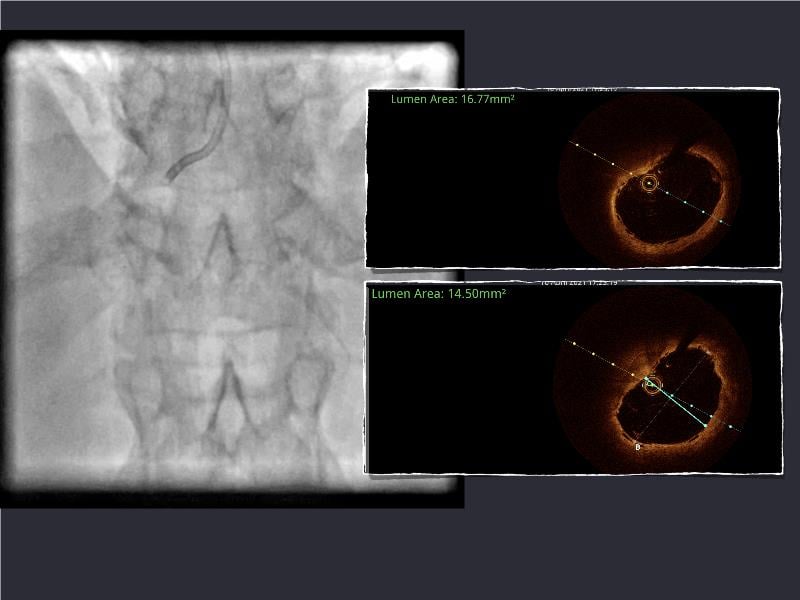

- To understand novel tools and techniques for effective management of bifurcation lesions and long diffused lesions using dedicated stenting solutions